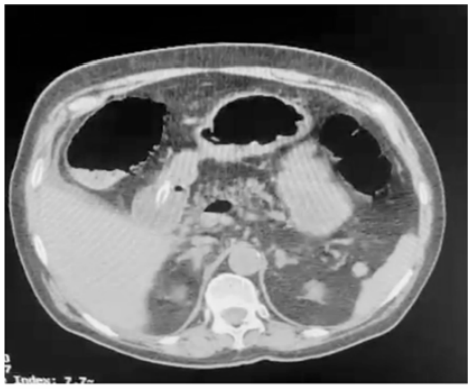

Um paciente de oitenta anos de idade, já com grau de perda de funcionalidade, com períodos de esquecimento, chegou ao pronto-socorro com queda importante do estado geral, com poucas informações objetivas, porém com dor ao exame físico de abdômen. Difícil interpretação dos sinais de irritação peritoneal. Realizou a tomografia abaixo.

A principal causa desse achado é o(a)